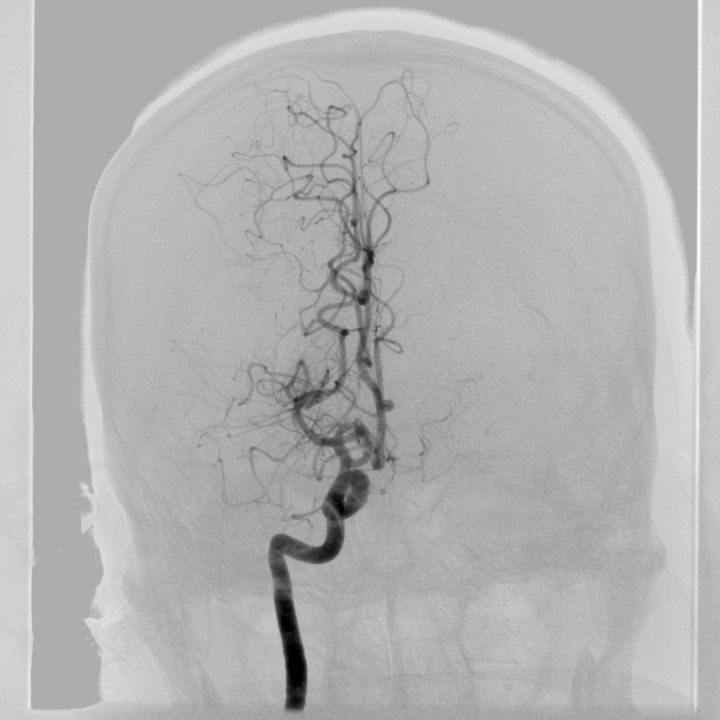

急性缺血性腦卒中急診取栓

取栓前

取栓后